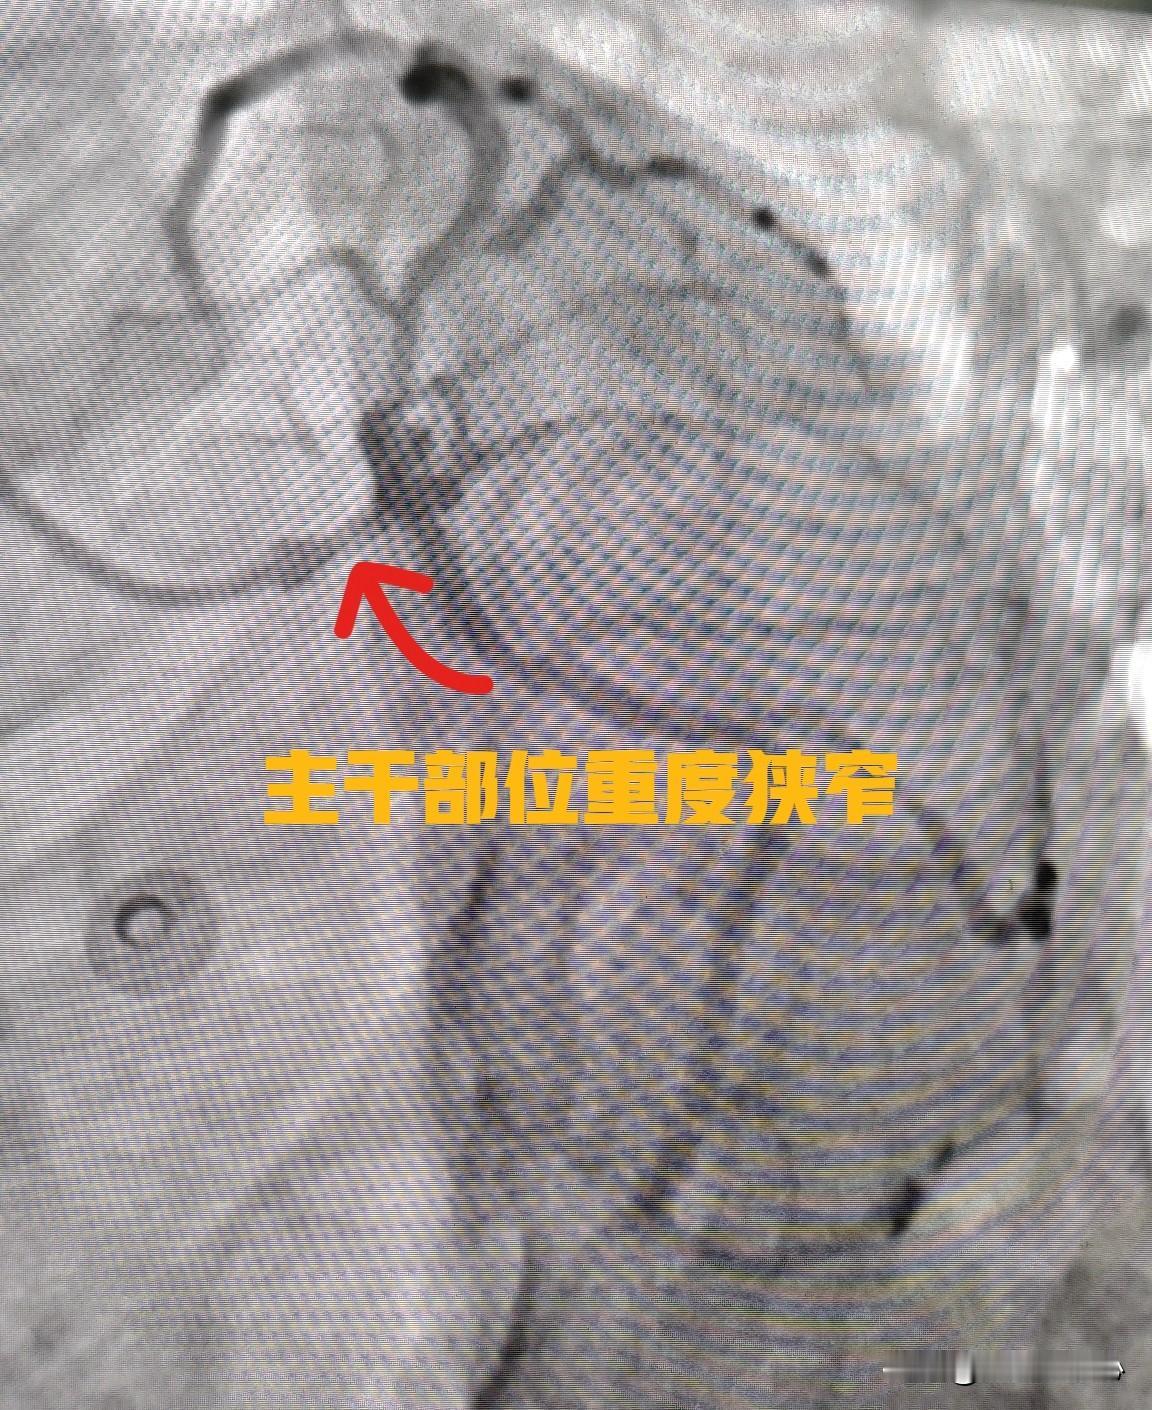

冠心病总体来讲有三种治疗方案,第一种就是药物治疗,药物治疗的主要目的是缓解心绞痛症状,通过药物阻止动脉硬化斑块进一步加重,降低心肌梗死的风险。 第二种治疗方案就是冠状动脉介入治疗加药物治疗。通俗地说就是做心脏支架,通过心脏支架把狭窄的冠状动脉撑开。让血液能正常通过,改善心脏的供血。同时规范服用冠心病的相关药物,比如阿斯匹林、氯吡格雷,他汀等等。 第三种治疗方案就是心脏搭桥手术。用身体自身的血管绕过心脏血管的堵点,给远端的肾脏血管供序。就像堵车了,换另外一条路也能通过一样。 从上面三种治疗方案来看,冠心病的保守治疗就是指单纯的药物治疗,药物治疗能解决大部分的冠心病。只有心脏血管堵的特别严重的,才需要心脏支架手术或者是搭桥手术。 像图片这种情况就不适合药饱受治疗和心脏支架手术了。这个患者是左主干重毒狭窄,同时其他血管也有很严重的狭窄,支架手术的风险很高。建议患者做了心脏搭桥手术。 心脏介入支架 冠心病